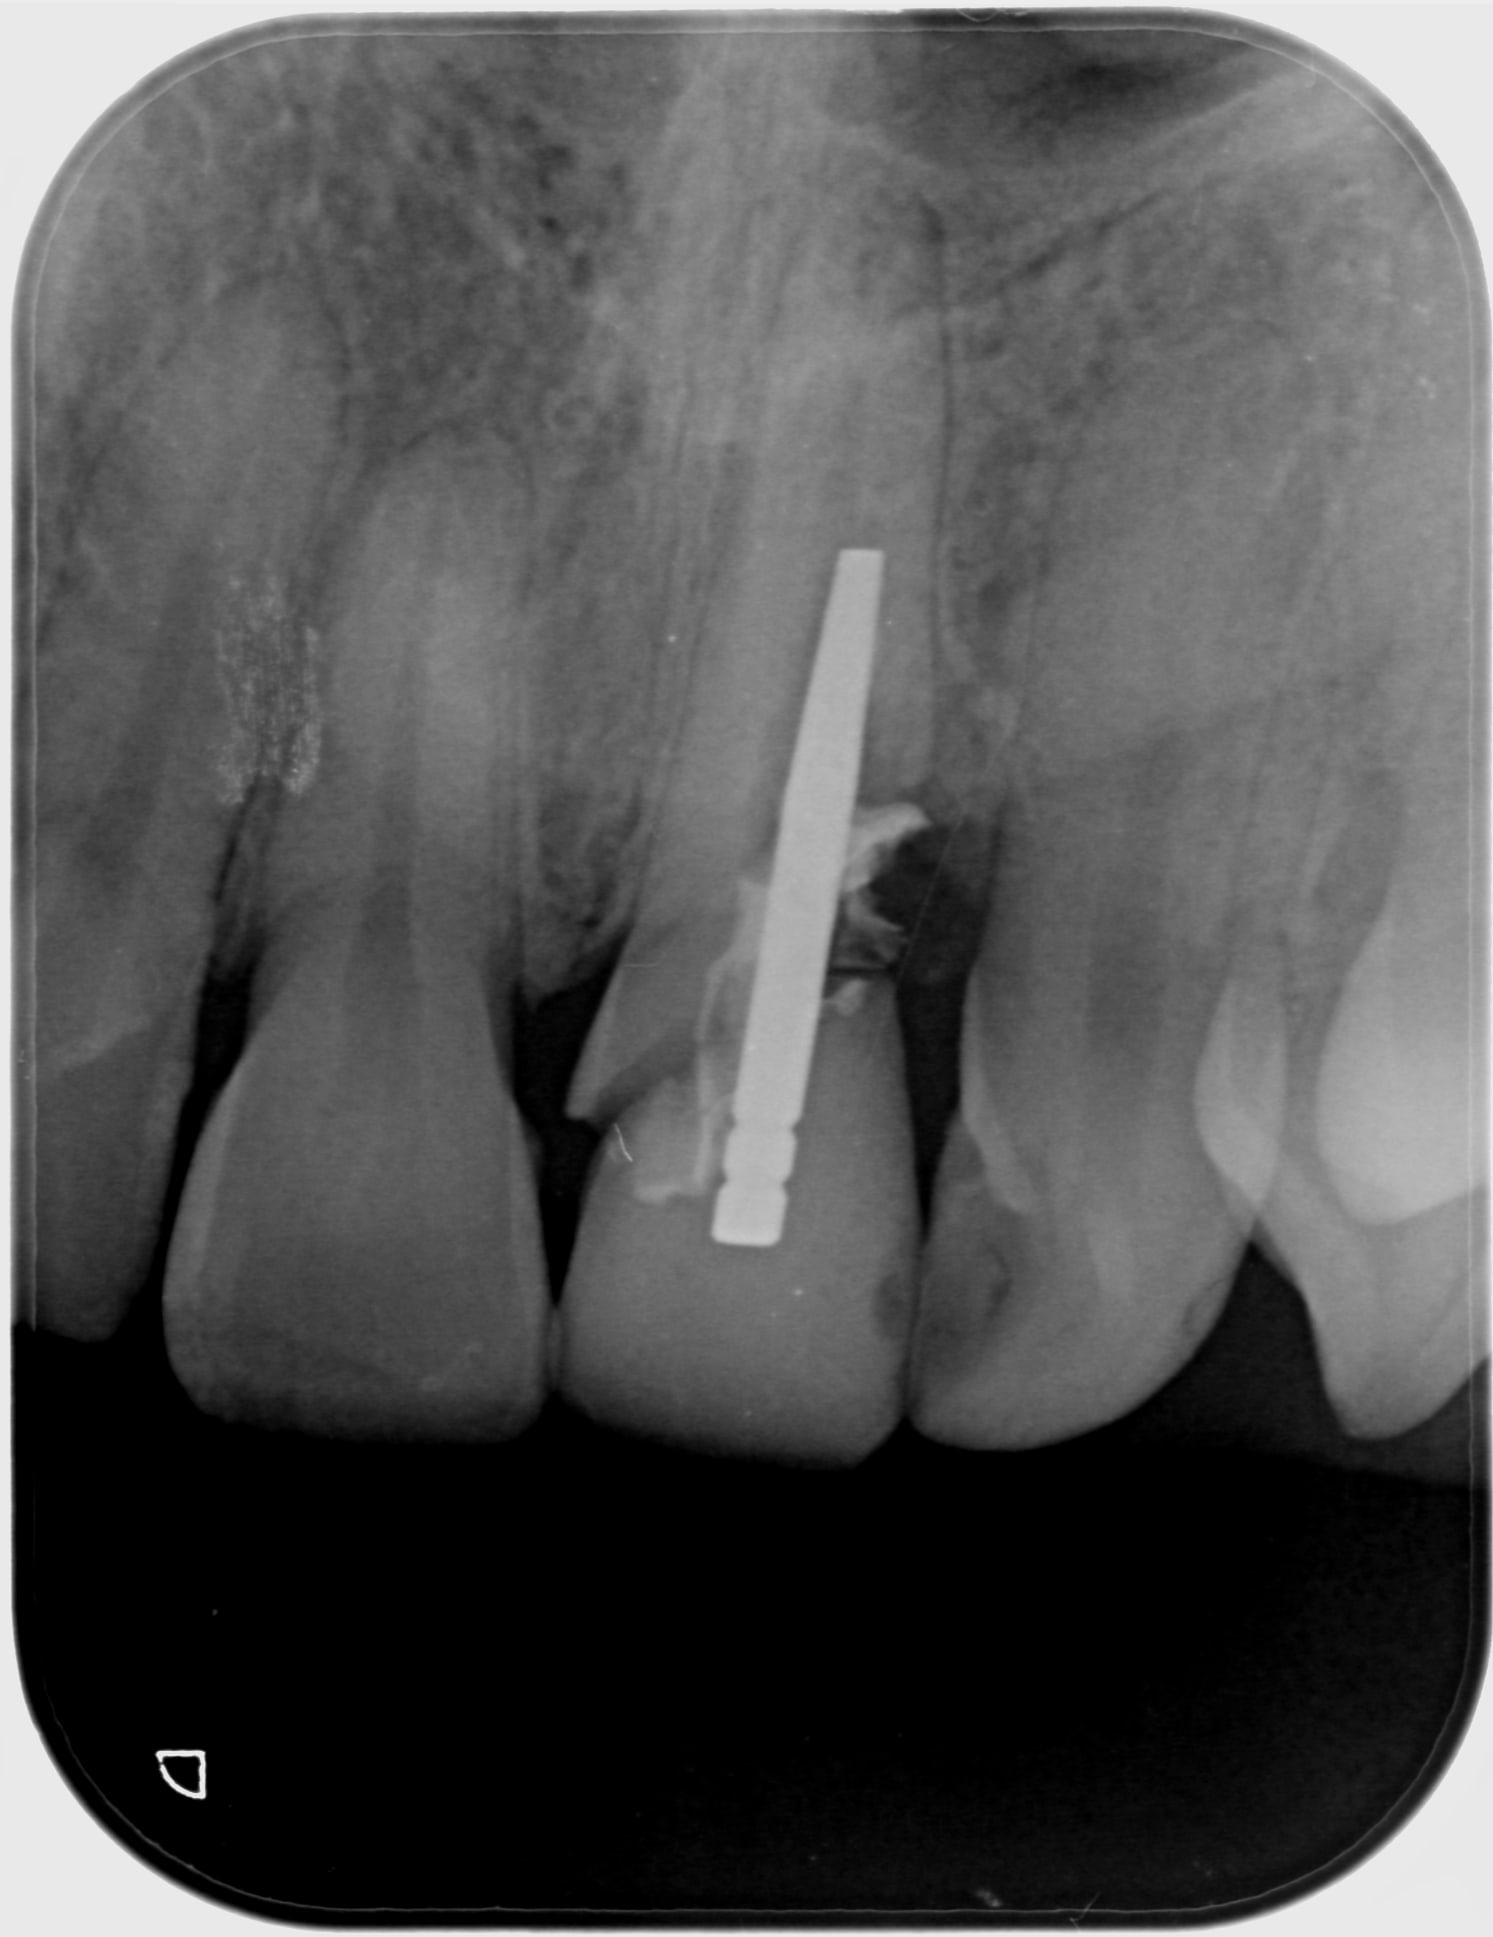

Les rétros

2015 05 29 retro avant exo x9afby - Eugenol

2017 01 04 exo uklgb2 - Eugenol

2017 05 03 retro preop dadb2g - Eugenol

2017 11 09 retro jour pose hwdyvj - Eugenol

2017 11 15 retro j 7 x3s3zc - Eugenol